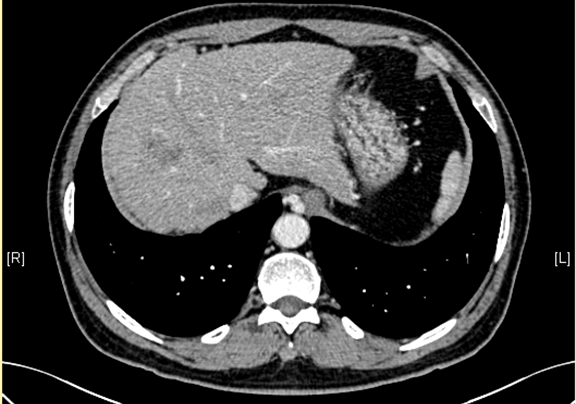

术前CT检查:

动脉期

下腹部增强CT示:肝右叶恶性肿瘤可能性大;肝内多发小囊肿;肝硬化,食管胃底静脉曲张可能性大;脾脏囊肿可能性大。